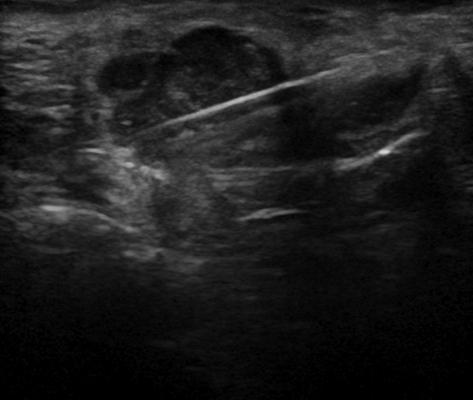

U tuyến nước bọt

» Thông tin: Nam giới – 72 tuổi.

» Lâm sàng: Khối vùng mang tai.

# Ung thư biểu mô tuyến (Adenocarcinoma).